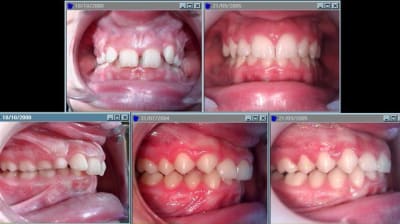

Pour adhoc , deux exemples de traitement par activateur SB.

Le premier montre la levé de supra dans une 2.2.

Ce qui est interessant , c'est de voir que la supra, en même temps que la correction de la classe 2 ( double effet kiss cool ), c'est effectuée en permetant la poursuite de l'éruption physiologique des 6.

Et pas seulement par ingression incisive, comme avec un arc de base.

Le traitement n'est pas fini, il reste encore de la supra, et à carrer la mandibule, selon les critères d'équilibre de Planas.

Sb classe2.2 - Eugenol